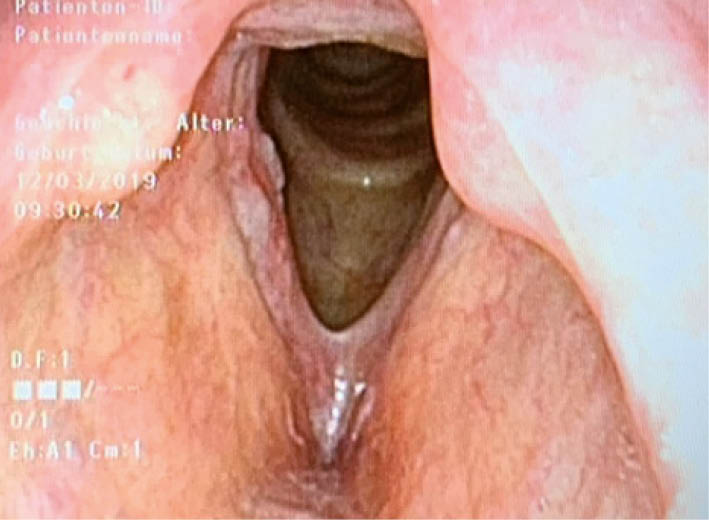

Chronische Laryngitis (Abb. 1):

Bei chronischem Nikotinkonsum (als weitere ätiologische Faktoren werden auch ein gastro-ösophagealer Reflux, Allergien, Irritation durch trockene staubige Luft oder ätzende Dämpfe, Mundatmung oder fehlende Stimmschonung nach akuter Laryngitis diskutiert).